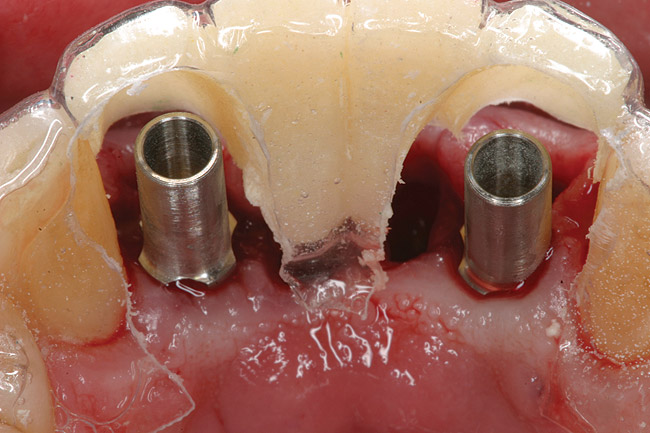

Figure 4  Tapered implants with conical transgingival abutments and temporary cylinders in place.

Figure 4